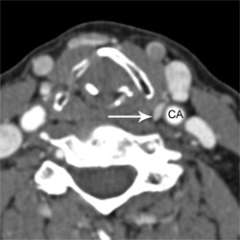

Figure 1a. Parathyroid 4D-CT showing a parathyroid adenoma in an abnormal position within the carotid sheath, missed during a prior surgery. CA= Carotid artery.

Figure 1b. Parathyroid 4D-CT showing a parathyroid adenoma in an abnormal position within the carotid sheath, missed during a prior surgery. CA= Carotid artery.